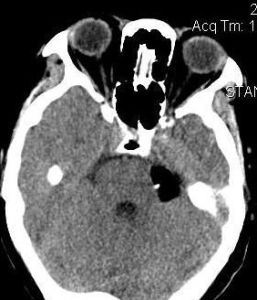

3、CT和MRI掃描

CT見瘤體為邊界清楚、形態不規則、呈均勻的低密度影,少數為混雜密度。增強後無強化。MRI在T1加權上表現為略高於腦脊液的低信號影,T2加權上為略低於腦脊液的高信號。注射增強劑後囊腫無強化為其特徵。

2、CTCT掃描是表皮樣囊腫的有效診斷手段。有助於發現腫瘤輪廓及擴張情況,囊腫表現為低密度影像。一般注射增強劑後不強化。板障內表皮樣囊腫可呈膨脹性破壞,邊緣銳利的混雜密度影像。3、MRI表皮樣囊腫在T1加權像上顯示邊界銳利的低信號,T2加權像上表現為高信號,腫瘤質地不均勻致信號強度變化不定,這是其在MRI的特徵。板障內表皮樣囊腫MRI可顯示其占位效應並可見高信號影像。